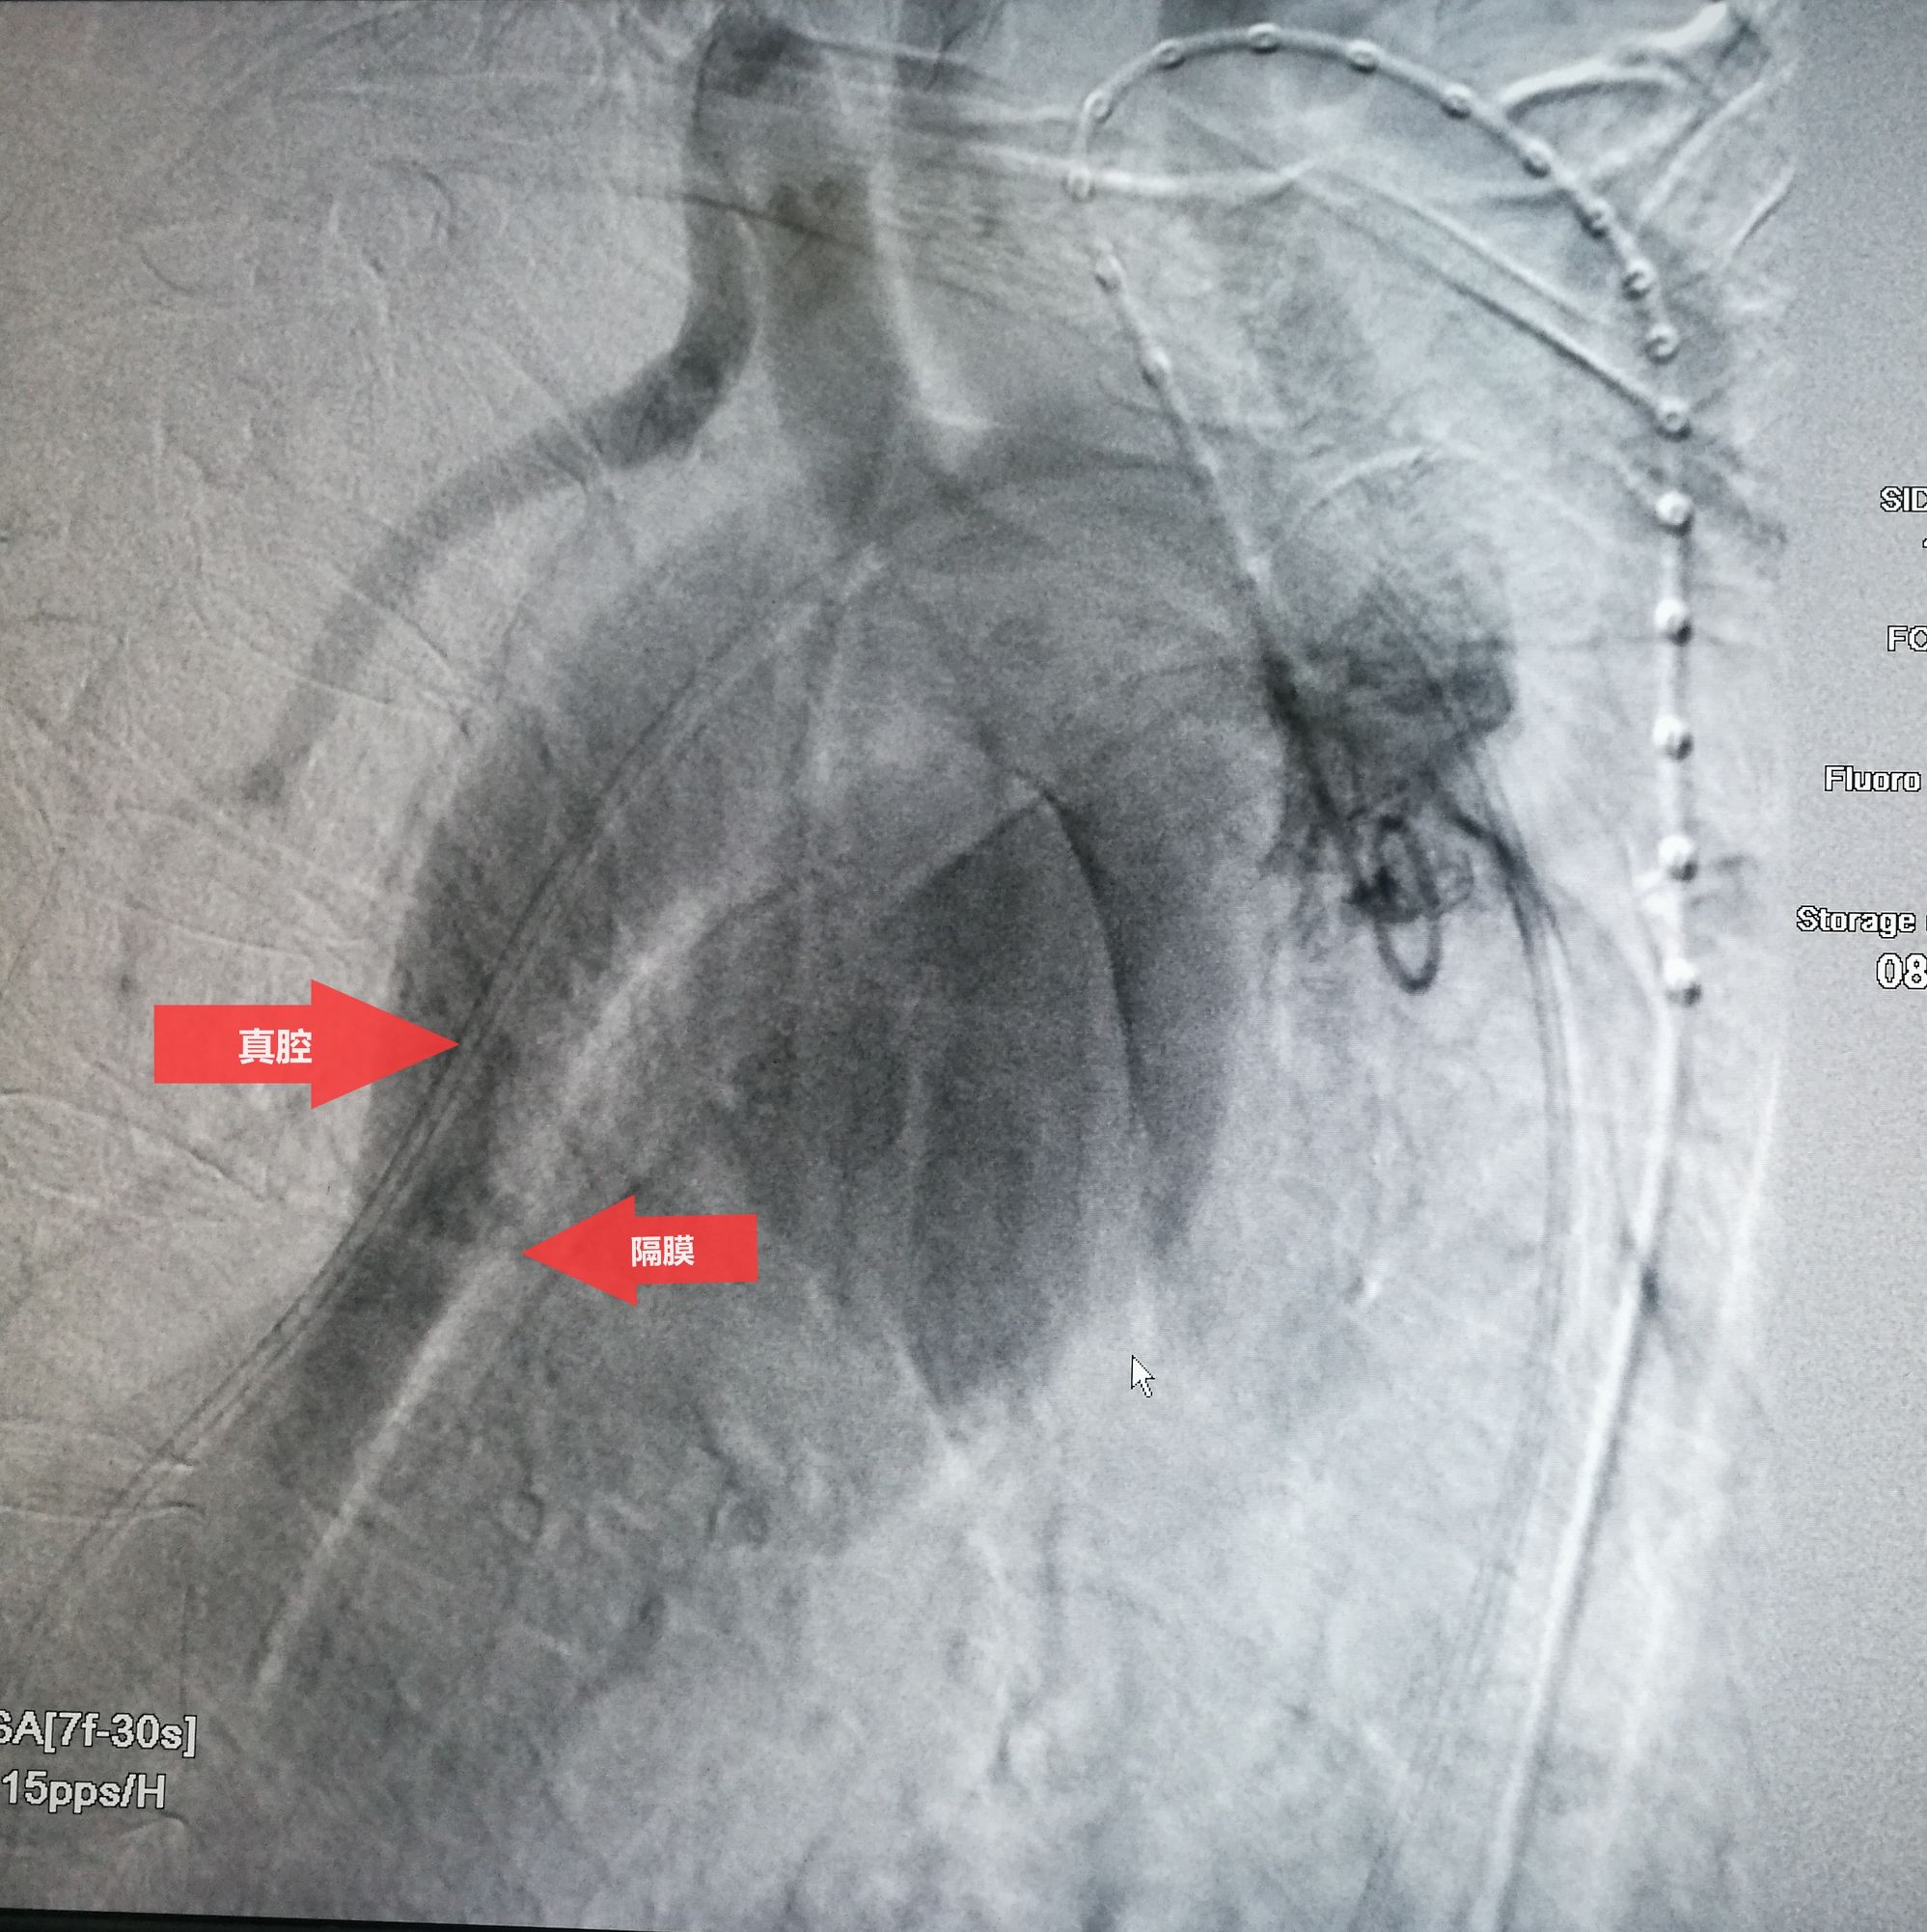

手术在局麻下进行,经右股动脉穿刺置管到升主,经左桡动脉穿刺植入金标猪尾导管,造影,为确认真假腔,加做右前斜位造影,确认股动脉导管在真腔内,测量后植入覆膜支架。由于扭曲严重(腹主,膈肌附近,弓降),支架最初并未贴服大湾侧,支架送过锁骨下动脉后适当回撤,请拉释放导丝,此时支架整体向大弯侧轻微移动,考虑应力已经得到缓解。完全释放支架,定位良好,封堵完全无内漏。

此例患者进行发病时未能确诊,进入慢性期后假腔扩张瘤样变。在CT的部分层面,食道受压看不到。重建影像可见假腔扩张,动脉扭曲。